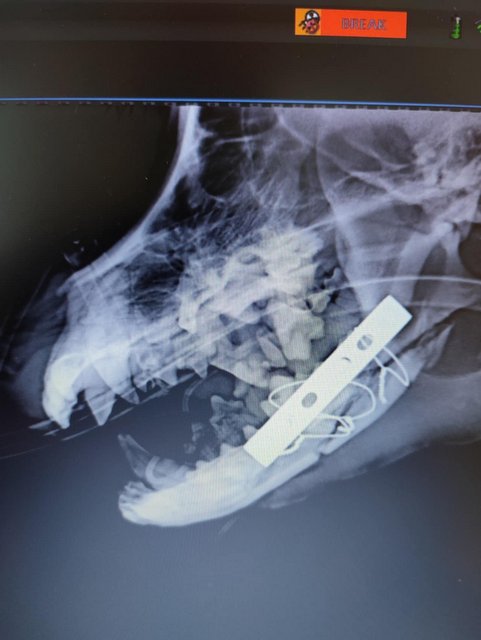

Camush Kopf ist wieder symmetrisch, der Kiefer wird jetzt mit Platte und Verdrahtung zusammengehalten und ein paar Zähne fehlen jetzt.

Röntgenbilder zeigten das Ausmaß der Zerstörung des Unterkiefers und den Bruch eines Beines.

Dieser Hund muss grausame Schmerzen haben, Zähne sind aus der Verankerung gerissen und sein Gesichtsschädel ist nicht mehr symmetrisch. Ein großes Stück des Unterkiefers ist komplett abgebrochen.

Es braucht sicher viel Geschick, um das wieder so zusammenzusetzen, dass der Hund später problemlos fressen kann.